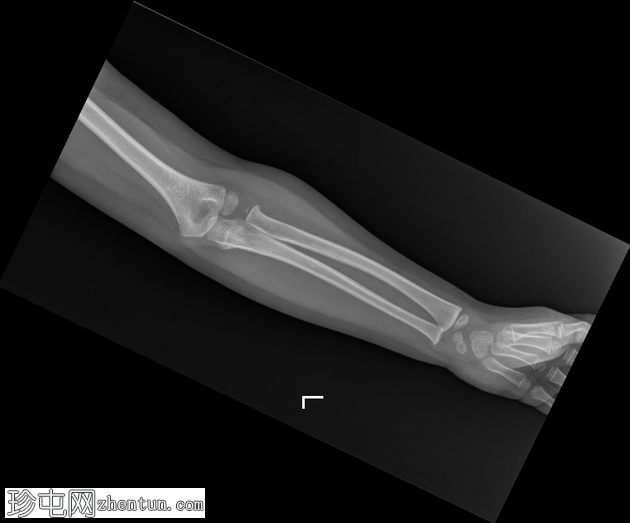

X光片

1.png

正面

在正位片和侧位片上,桡骨近端干骺端可见轻微的皮质断裂和不规则,骨折线似乎向骺端延伸。

相关的脂肪垫征(可见前脂肪垫和帆状征,后脂肪垫阳性)进一步支持骨折后关节内积液的存在。

总体而言,骨性对线保持良好,无脱位迹象。

骨化中心与年龄相符。